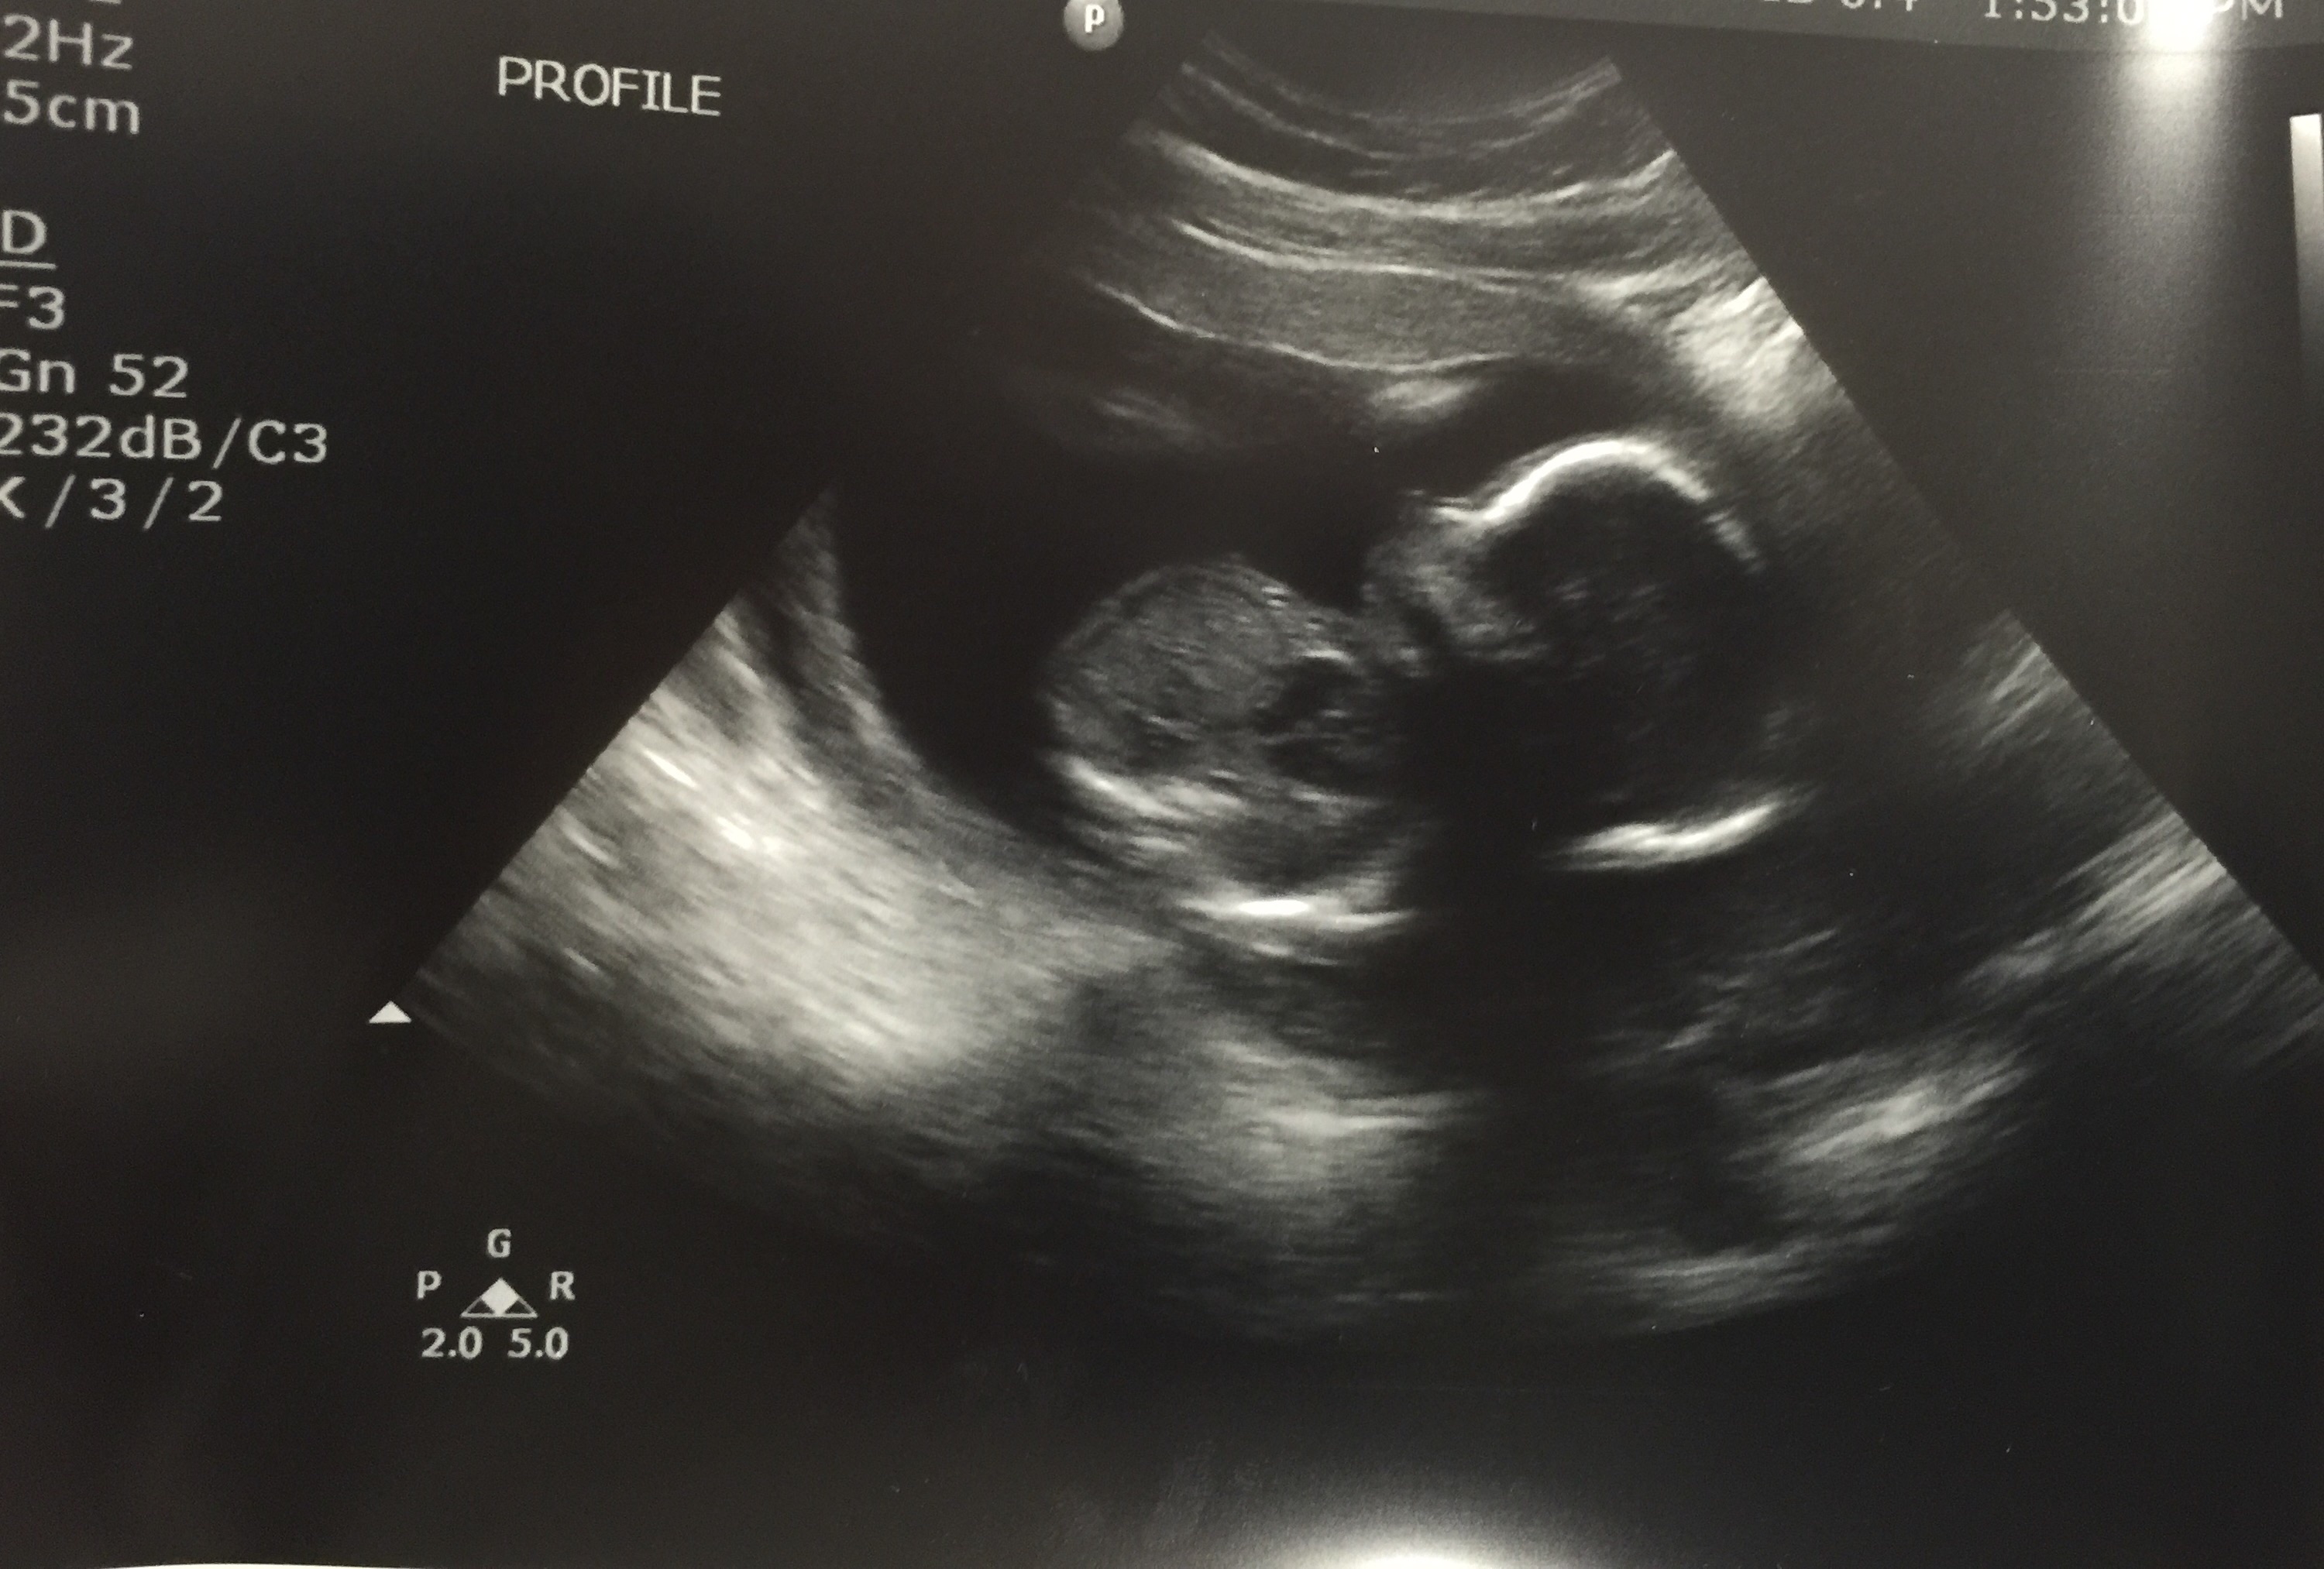

When she finally arrived and wheeled me back I begged her to please tell me something. Anything! I told her I just wanted to know if she saw a heartbeat. She told me that it was against the rules to give me any information. I sat there clutching my St. Gerard medal and praying while she conducted the longest and most detailed ultrasound of my life. To my surprise, she turned the screen toward me and said, “Don’t tell anyone I showed you this, but I just can’t believe how cute it is. It looks like the baby is waving.”

Sure enough, my little troublemaker was moving the top half of his or her arm from the elbow joint and appeared to be saying, “Hi Mom. Sorry for all the trouble.” All I could do was laugh. This was my first true mom moment where I couldn’t even be mad at the unnecessary ruckus because I was just so damn glad to see that everything was OK. I felt such a great sense of relief as I got wheeled back to my room to wait on the doctor.

The tech showed me my sweet little angel bee bopping around in the womb and told me that this baby was “clearly not bothered” by anything that was going on. We listened to the heartbeat on the ultrasound and the doctor remarked that it “sounds like a girl but don’t paint the room pink just yet.” I told him that I figured only a girl could bring this much drama with her. Either that or she is determined to have her picture taken every week until she makes her debut. We had a good laugh about that.

Baby P, who is clearly not bothered by any of this.